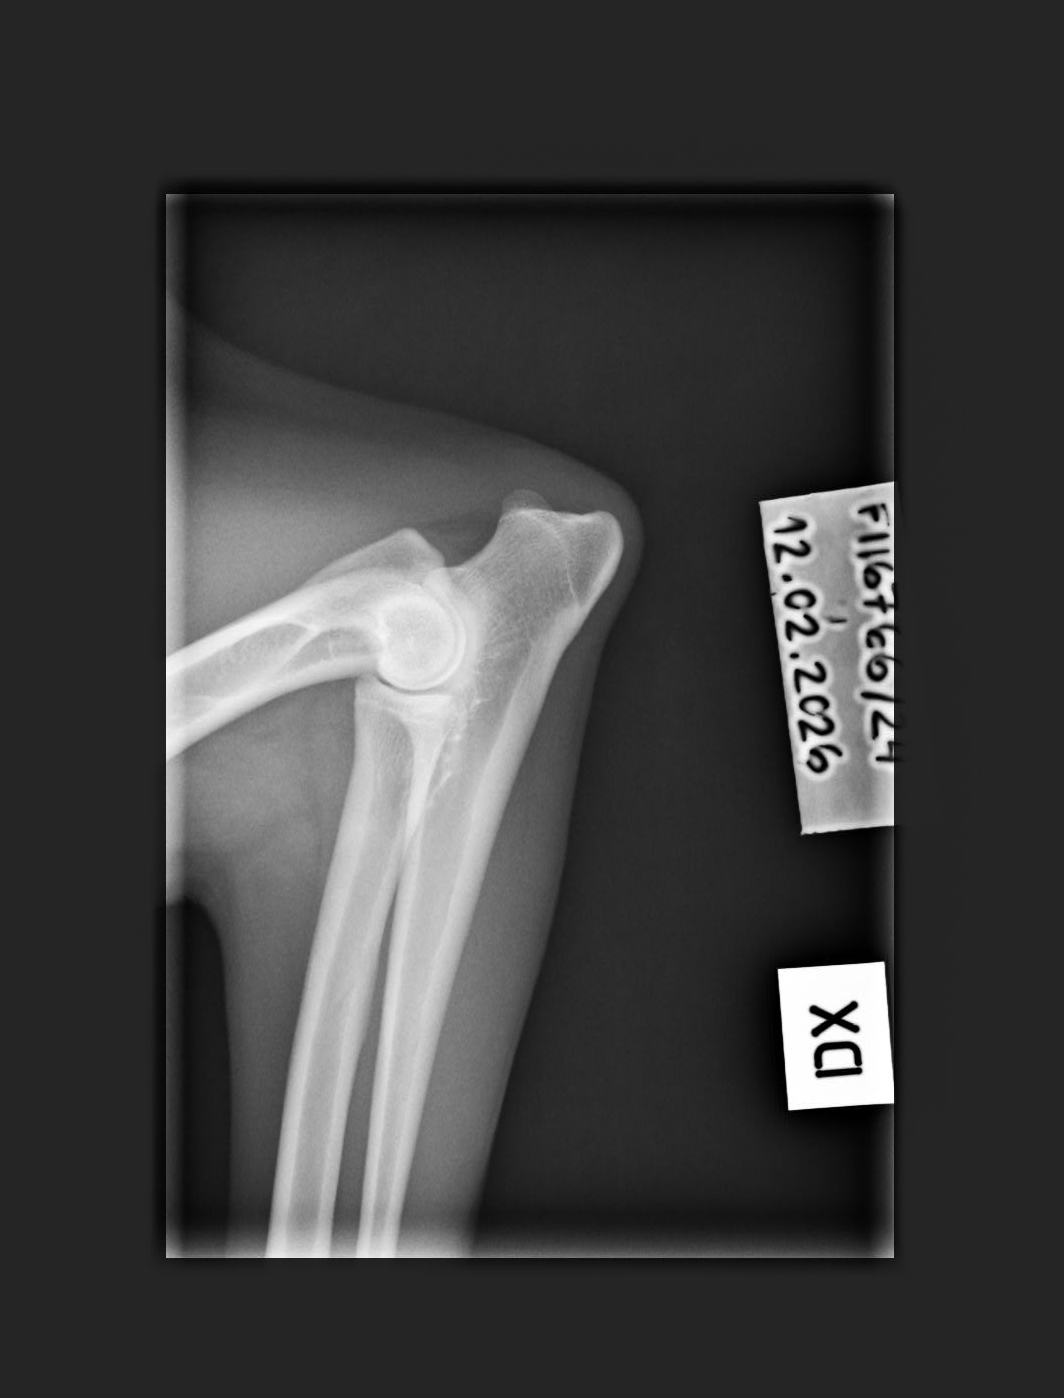

NHAT Pihlajamäen Aslan ♂ Personal

C/B |

1/0 (see Notes) |

- Finnish Kennel Club's elbow x-ray report Dec '25: Signs suggestive of medial coronoid disease; further information about the condition of the joints can be obtained, if necessary, by computed tomography (CT) examination

- Finnish Kennel Club's elbow CT report Feb '26: A small amount of new bone formation around the medial coronoid process of the left elbow